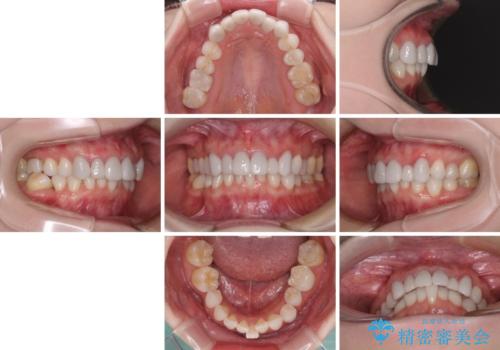

気にしていた歯並びをインビザラインで改善 セラミックも作り替えて綺麗な口元に

- 全体的なデコボコと、奥歯の欠損を放置した結果倒れ込んだ奥歯などを気にして来院された患者様です。

ワイヤー矯正の方が理想的な仕上がりとできる状態でしたが、上顎前歯にクラウンが装着されているため、インビザラインにて矯正治療を行うこととしました。

矯正治療自体はインビザラインで満足のいく仕上がりとなりました。

欠損部位は傾斜歯軸を起き上がらせることができたため、オールセラミッククブリッジにて補綴治療を行いました。

全顎的に満足のいく仕上がりとなりました。